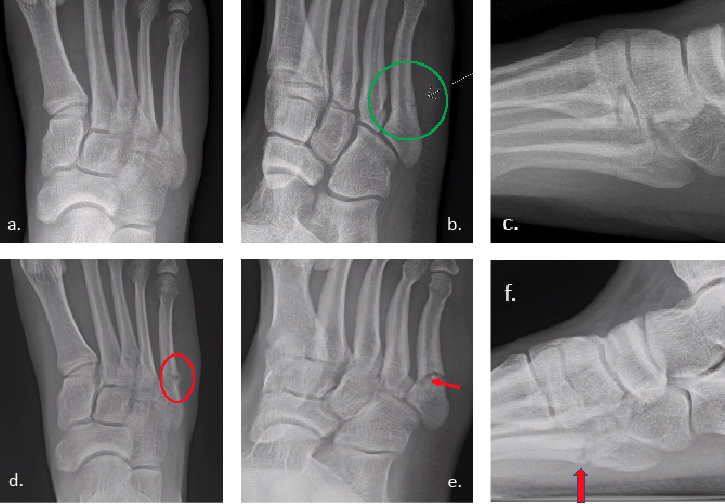

As a longtime sports fan, I have seen how Jones fractures (Figure 1) can alter the success of a season and change the careers of athletes across professional and collegiate sports. The majority do return to their sport, but some do not, with multiple surgeries, nonunions or refractures complicating the course.

It is important to recognize the age of the fracture. I have noted radiologists routinely mistaking acute fractures for stress fractures based on location. I’ve heard surgeons tell patients that their fracture isn’t healing based on a 6-week-old injury, due to signs of bone resorption, which is normal sign of healing. Unfortunately, not all Jones fractures get X-rayed the same week, let alone within a month of the injury, so they may present already showing signs of radiographic healing. Either way, I find it is common that one may overread the imaging. See Figures 2-3.